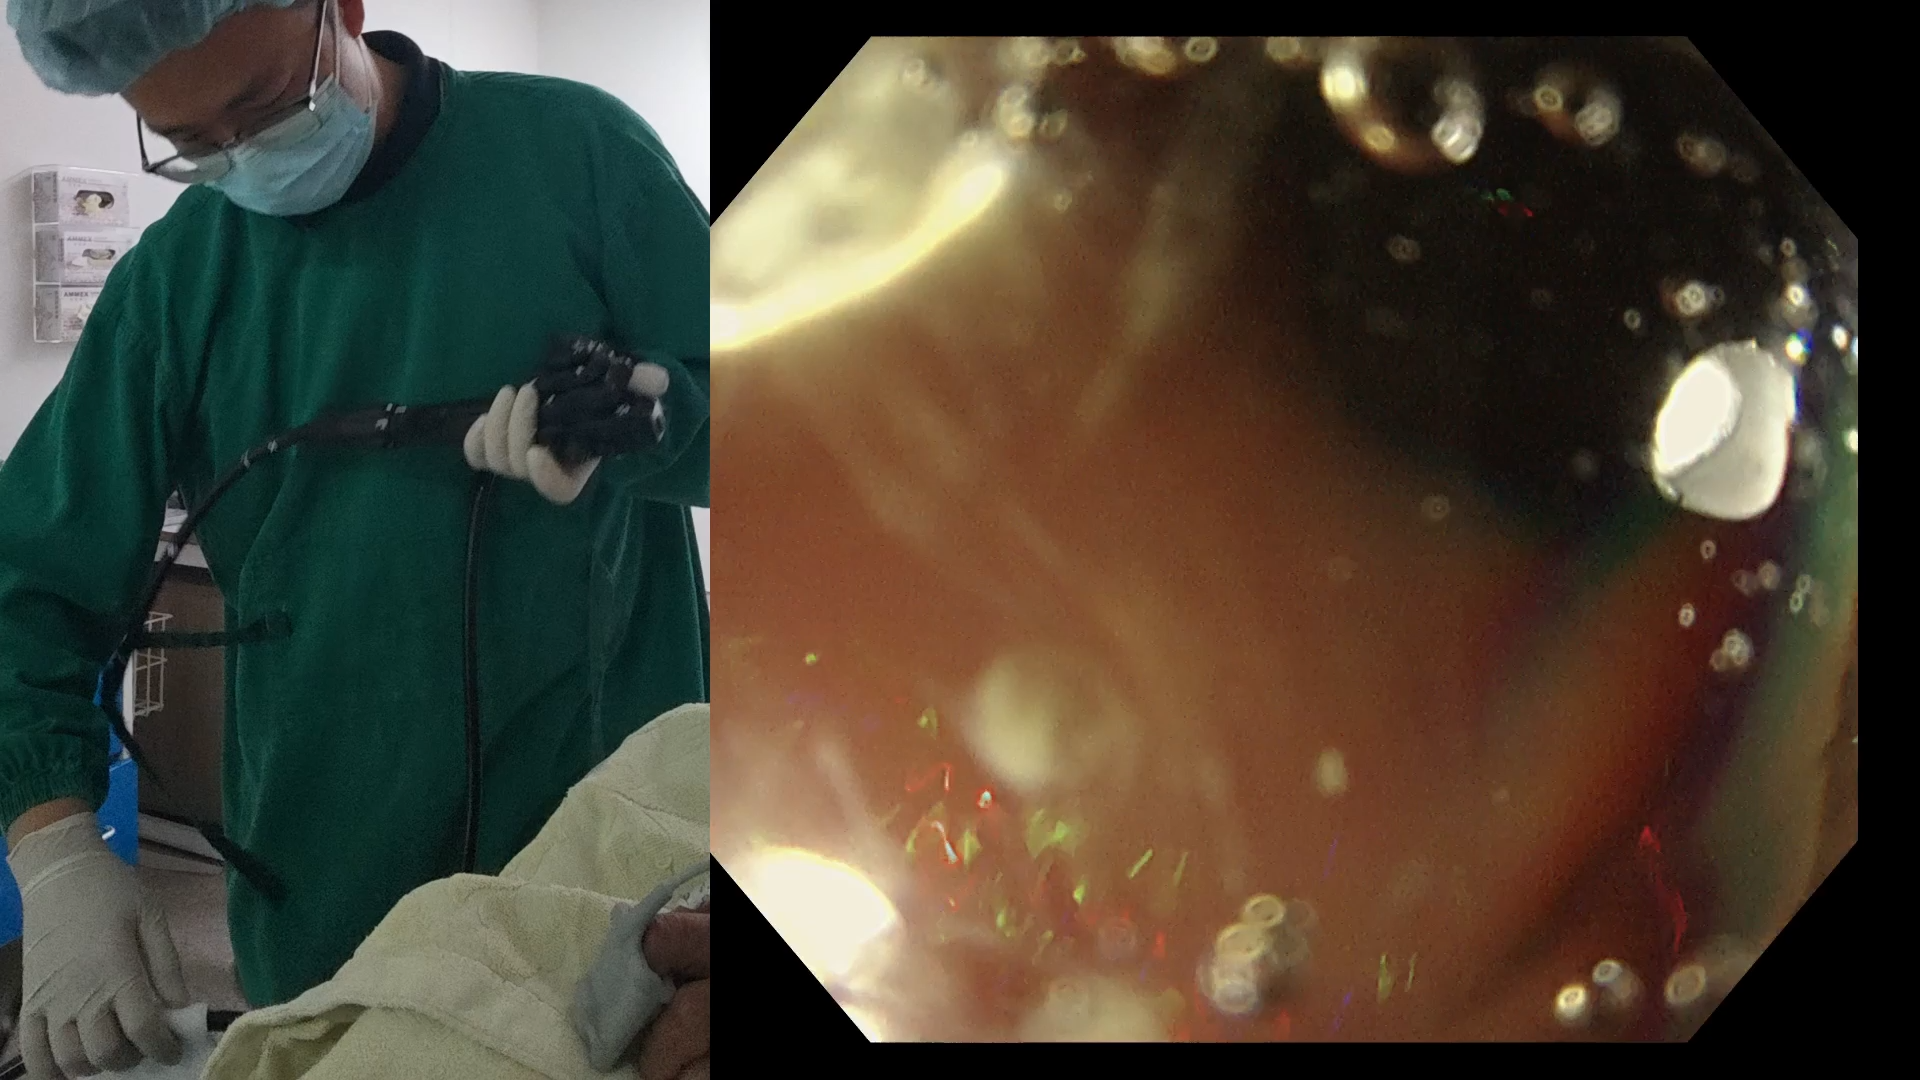

病例双画面切息肉(25)——多发小息肉

60+男性

碰到多发小息肉,你在实际操作中的做法是?

上周六“双画面切息肉(24)——带蒂”评论区讨论见本期答案